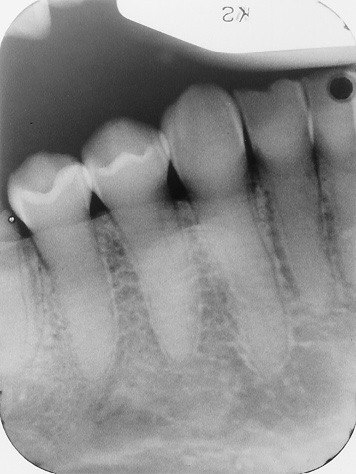

1. What is the condition in the distal surface of the tooth # 4.6?

2. What is the condition in the distal surface of the tooth # 4.7?